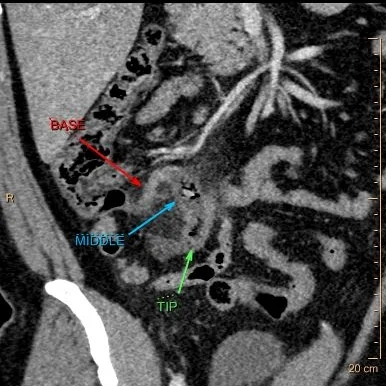

Going back to the CT scan on our patient, note the base of the appendix is normal, and there is a lot of inflammation around the middle of the appendix, where there is a small appendicolith. There is markedly decreased iodine uptake in the wall, and on the iodine map, there is no uptake where the normal wall should be. This is a clearly perforated appendix!

Path report : "Pink-tan to hemorrhagic and rough with an area of perforation in the middle appendix."

Conventional CT: Note obviously inflammed mid-appendix with small lith.